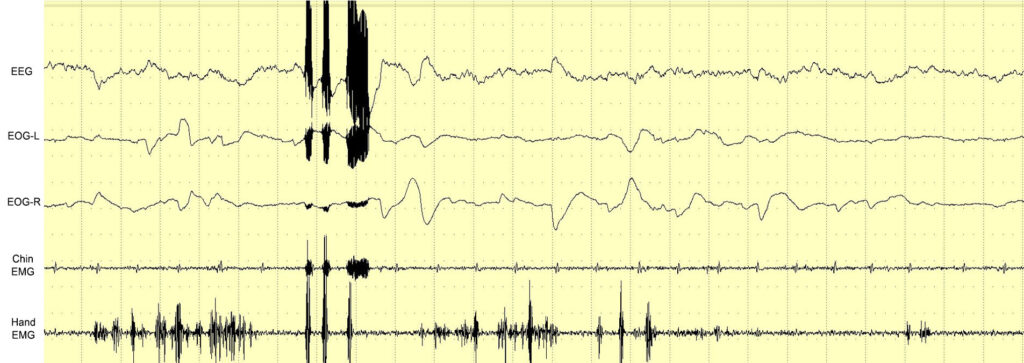

As humans spend one-third of their lives asleep, many studies have explored the possibility of controlling dreams. For the first time, we tested electrical brain stimulation (EBS) of the motor cortex during REM sleep to observe how it is incorporated into dreams. Electrodes were implanted in the motor cortex of one man with the ability to induce lucid dreams (LDs). Under polysomnographic (PSG) observation, the cortex was stimulated by an alternating current during REM sleep, sleep paralysis (SP), and lucid dreams (LDs). The results show that, within a certain current range, EBS did not wake the participant. Though he could not recall specific motor stimulations in REM sleep, some irregular changes in dream plots were observed. The most interesting results were observed during an LD in which it was possible to intentionally observe an EBS-induced contraction, which interacted with a dream object. In some cases, sensory feedback from the EBS of the motor cortex was perceived when the PSG data showed REM sleep and muscle atonia. Though some of the results need further confirmation, we discuss how the obtained data could present new horizons for controlling dream scenes and inducing LDs.

Testing in wakefulness and in dreams

Results